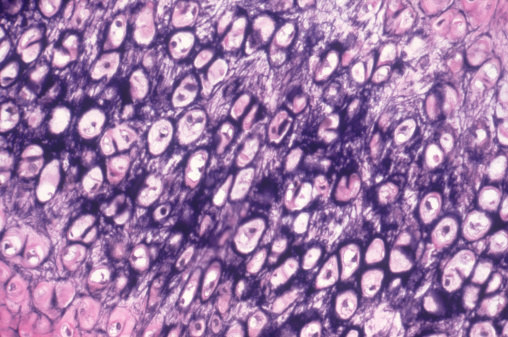

Doctors placed the ear-shaped tissue graft under a flap of skin, allowing it to form blood vessels before transplantation.

Biophoto Associates / Getty Images / Via gettyimages.com

The appearance of a transplant growing on or inside another part of the body may look shocking, but this procedure involves many of the same techniques used in routine plastic surgeries.

Surgeons often reconstruct body parts with "autologous tissue," which means they use a portion of skin, muscle, cartilage, or bone harvested from another region of a patient's body. Examples include postmastectomy reconstructive breast surgery and skin grafting for burn victims.

In this case, new external organs like an ear don't actually "grow," but are created from cartilage from elsewhere in the body and then placed in the body for some time before being moved to the new location.

The picture above depicts a man in China whose photo went viral in 2013 after surgeons opted to "grow" a new nose on his forehead after his nose was eaten away by an infection, ABC reports. Doctors used expanders to stretch the skin on his forehead and formed a new nose underneath the skin, using cartilage from his ribs. This allowed enough blood vessels to form so the new nose could be transplanted to the damaged region.